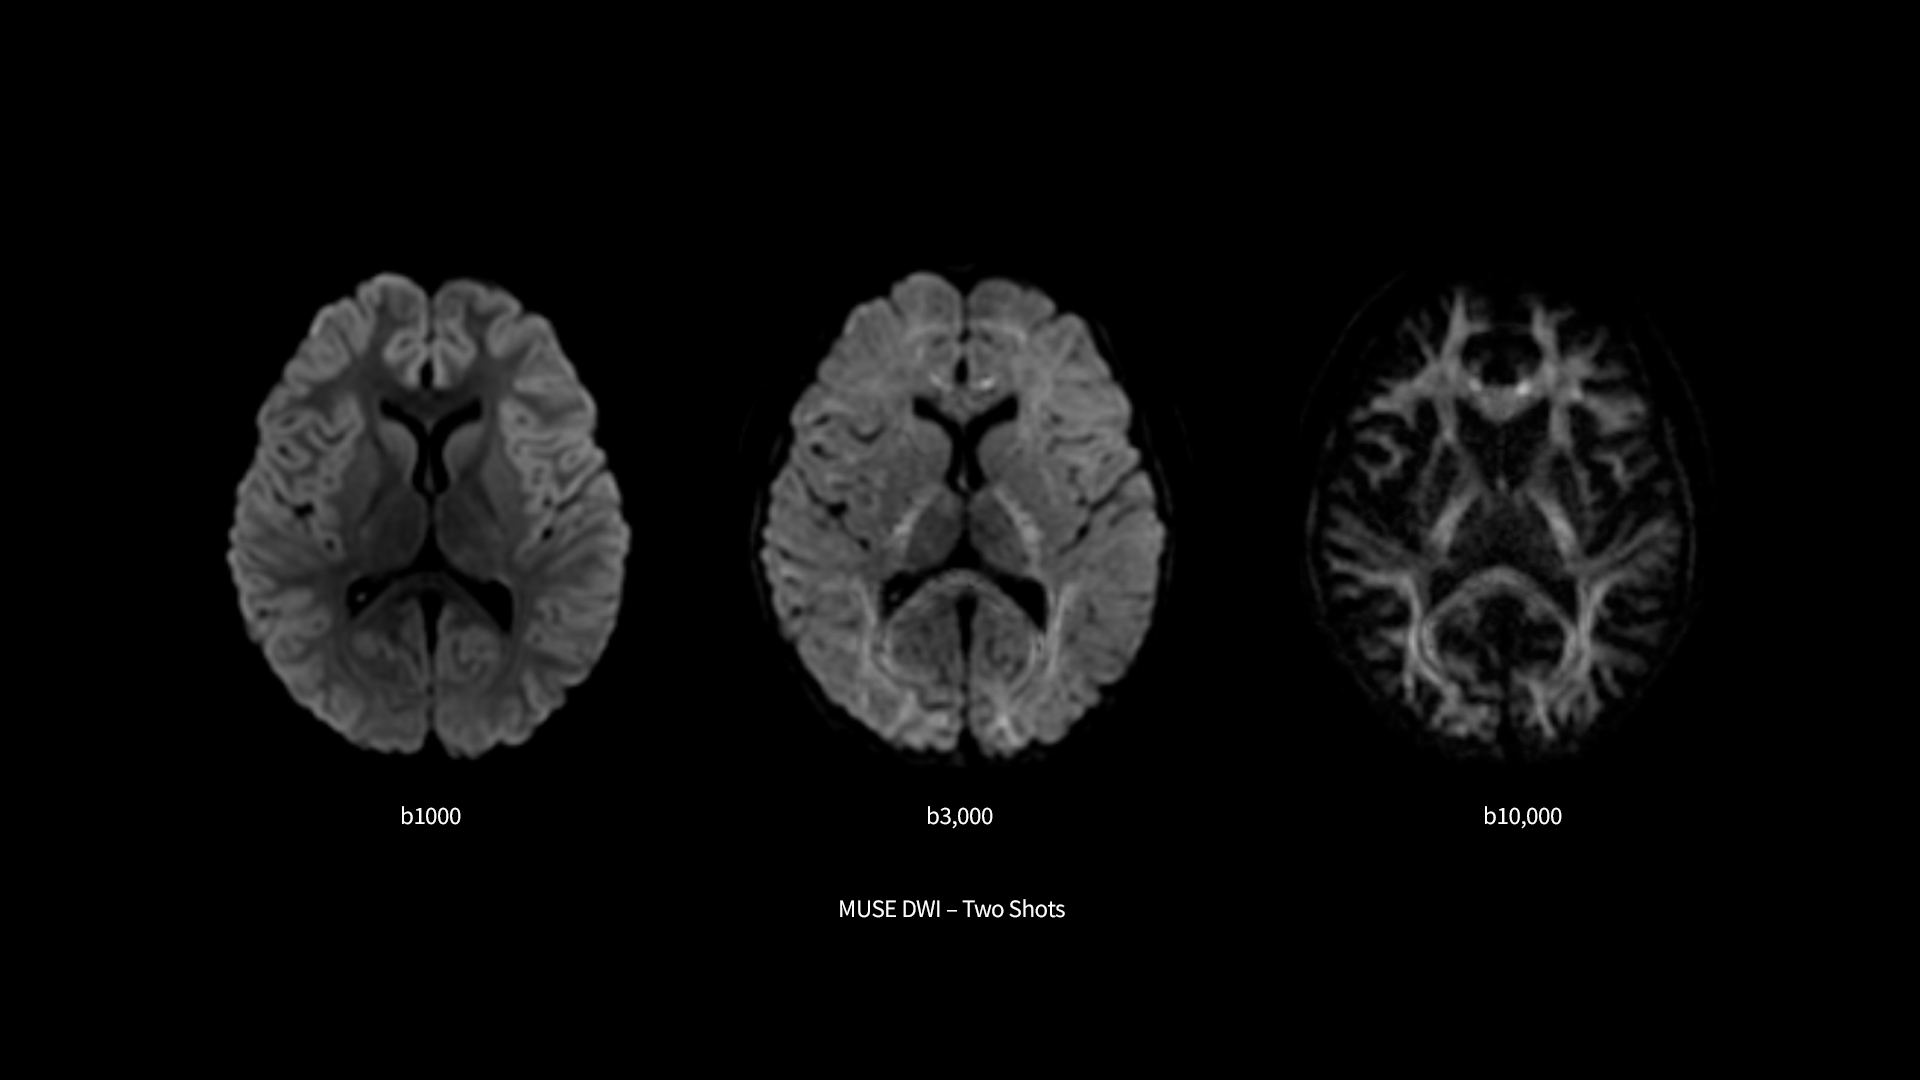

​SIGNA™ Premier supports the most demanding applications, such as Connectome-type studies that require Ultra-short TE diffusion imaging and high-resolution resting state fMRI. While it is a pioneering MRI system for cutting-edge research, it offers all the features needed to deliver routine clinical throughput. This includes delivering high end diagnostic image quality while ensuring the highest level of patient comfort.​

Pin-sharp image quality and exceptional speed with AIR™ Recon DL and Sonic™ DL​

SIGNA™ Premier offers the versatility you need to fulfill all your clinical needs. Explore the advanced imaging and clinical capabilities achievable with the SIGNA™ Premier system.

Experience pin-sharp precision and remarkable speed with a 3T SIGNA™ Premier MRI scanner, coupled with AIR™ Recon DL and Sonic™ DL.